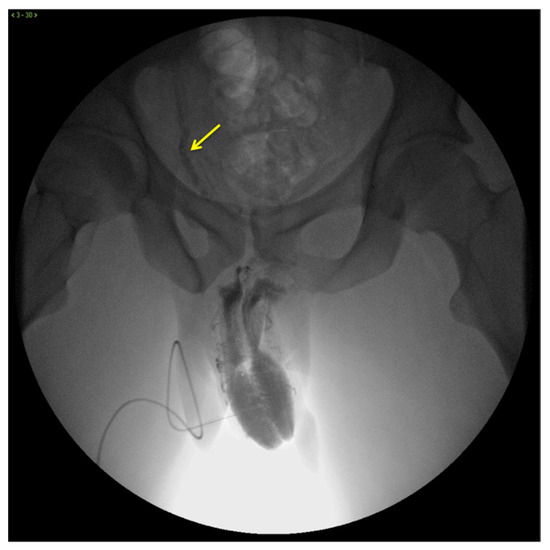

X-ray cavernosography is the first conventional radiographic examination useful to define a venous vascular map of the penis and to identify abnormal venous leaks (Figure 3) [19].

Figure 3.

Cavernosography. Frontal view. Partial EHS 3 erection with fast deep venous outflow with right dominance (arrow). EHS–erection hardness score.

However, this technique is extremely time-consuming and suffers from poor contrast and spatial resolutions with limited value in current clinical practice [12,15,20].